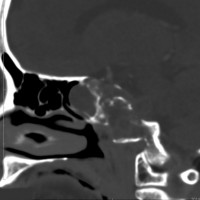

左動眼神経麻痺が急速に進行した例です。斜台から左海綿静脈洞,錐体骨尖を侵す頭蓋底軟骨肉腫です。左内頚動脈は腫瘍に取り囲まれています。

CTでは腫瘍実質部分が増強されます。不規則な骨破壊像・浸食像が特徴的です。

骨軟骨腫が若い時からあって壮年になってから悪性化した軟骨肉腫です。20代のときに右外転神経麻痺が生じて20年以上そのまま経過しました。左のCTでは頭蓋骨の真ん中の斜台というところに異常な骨があって,良性の骨軟骨腫のように見えます。でも右側のMRIでは脳幹部に深く食い込む柔らかい腫瘍の部分が写っていてこれは軟骨肉腫を疑う像です。手術摘出と術後の放射線治療をしました。